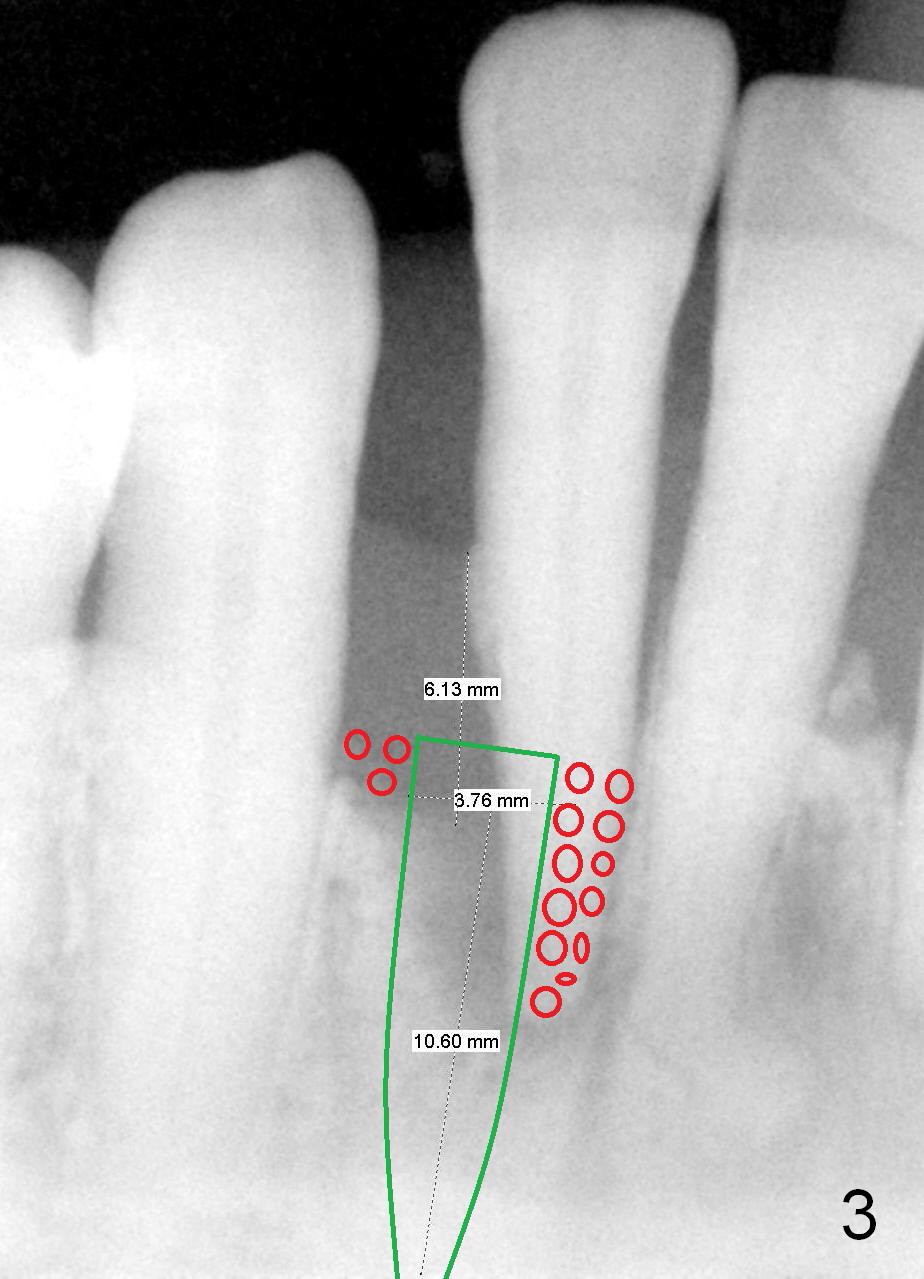

A 65-year-old lady has history of poliomyelitis and use of injection osteoporosis medicine. The tooth #26 is periodontally affected (Fig.1). Since the sensor is not placed deep enough (or there is plenty space above (Fig.1 arrow)), it is difficult to design implant treatment plan (Fig.2). PA has to be taken immediately pre-operatively for precise design.